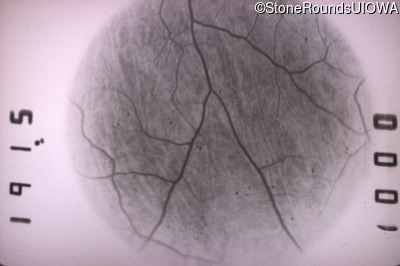

Infrared Fundus Photograph - Right - 20/40 -1

Exemplar